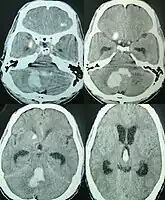

| CT scan of a spontaneous intracerebral bleed, leaking into the lateral ventricles | |

Intraparenchymal hemorrhage can be recognized on CT scans because blood appears brighter than other tissue and is separated from the inner table of the skull by brain tissue. The tissue surrounding a bleed is often less dense than the rest of the brain because of edema, and therefore shows up darker on the CT scan.[17]